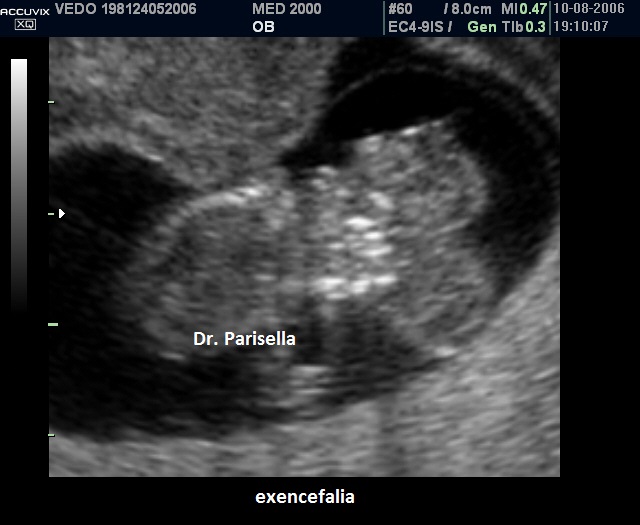

Nel I trimestre il processo distruttivo dell'encefalo non è ancora evidente per cui in questo periodo si osserva solo la mancata ossificazione delle ossa della volta cranica mentre gli emisferi cerebrali appaiono normali: si parla di acrania-exencefalia.

La diagnosi ecografica è relativamente semplice. A 11-12 settimane la volta cranica è assente mentre gli emisferi cerebrali sono ancora riconoscibili e circondati da una sottile membrana a diretto contatto con il liquido amniotico ( acrania-exencefalia ). In sezione coronale l'estremo cefalico assume un aspetto "a mickey mouse"determinato dalla visualizzazione degli emisferi cerebrali come due strutture semicircolari al disopra delle orbite.